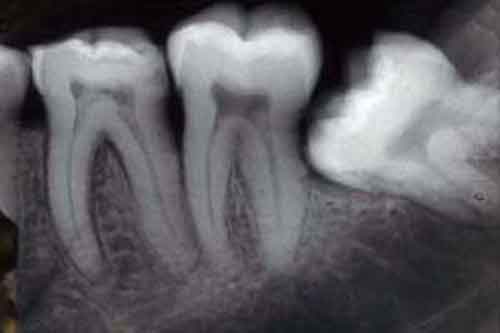

Radiografie ai denti: troppe, aumentano casi di tumori.

Le persone che hanno effettuato frequenti radiografie ai denti hanno maggiori possibilta’ di sviluppare un tumore al cervello.

L’autrice della ricerca e il suo team hanno analizzato le cartelle di 1.433 pazienti ammalati di eta’ compresa tra i 20 e i 79 anni tra il maggio 2006 e il 2011. Gli individui che hanno riferito di aver effettuato gli esami radiografici su base annua o piu’ frequentemente hanno avuto da 1,4 a 1,9 volte in piu’ di probabilita’ di sviluppare un meningioma. Il rischio aumentato di meningioma e’ apparso legato anche agli esami panorex su base annuale o effettuati frequentemente. Gli individui che hanno riferito di aver effettuato questi esami piu’ volte nell’arco di dieci anni hanno avuto un rischio 4,9 volte maggiore di sviluppare meningioma. I ricercatori hanno osservato che “oggi i pazienti che controllano i propri denti sono esposti a basse dosi di radiazioni rispetto al passato.

Tuttavia, questo st udio rappresenta l’occasione per riflettere su un uso piu’ moderato delle radiografie e soprattutto dilatato nel tempo: per i bambini una radiografia massimo ogni due anni, per i ragazzi una ogni 3 anni e per gli adulti una ogni 2-3 anni”.